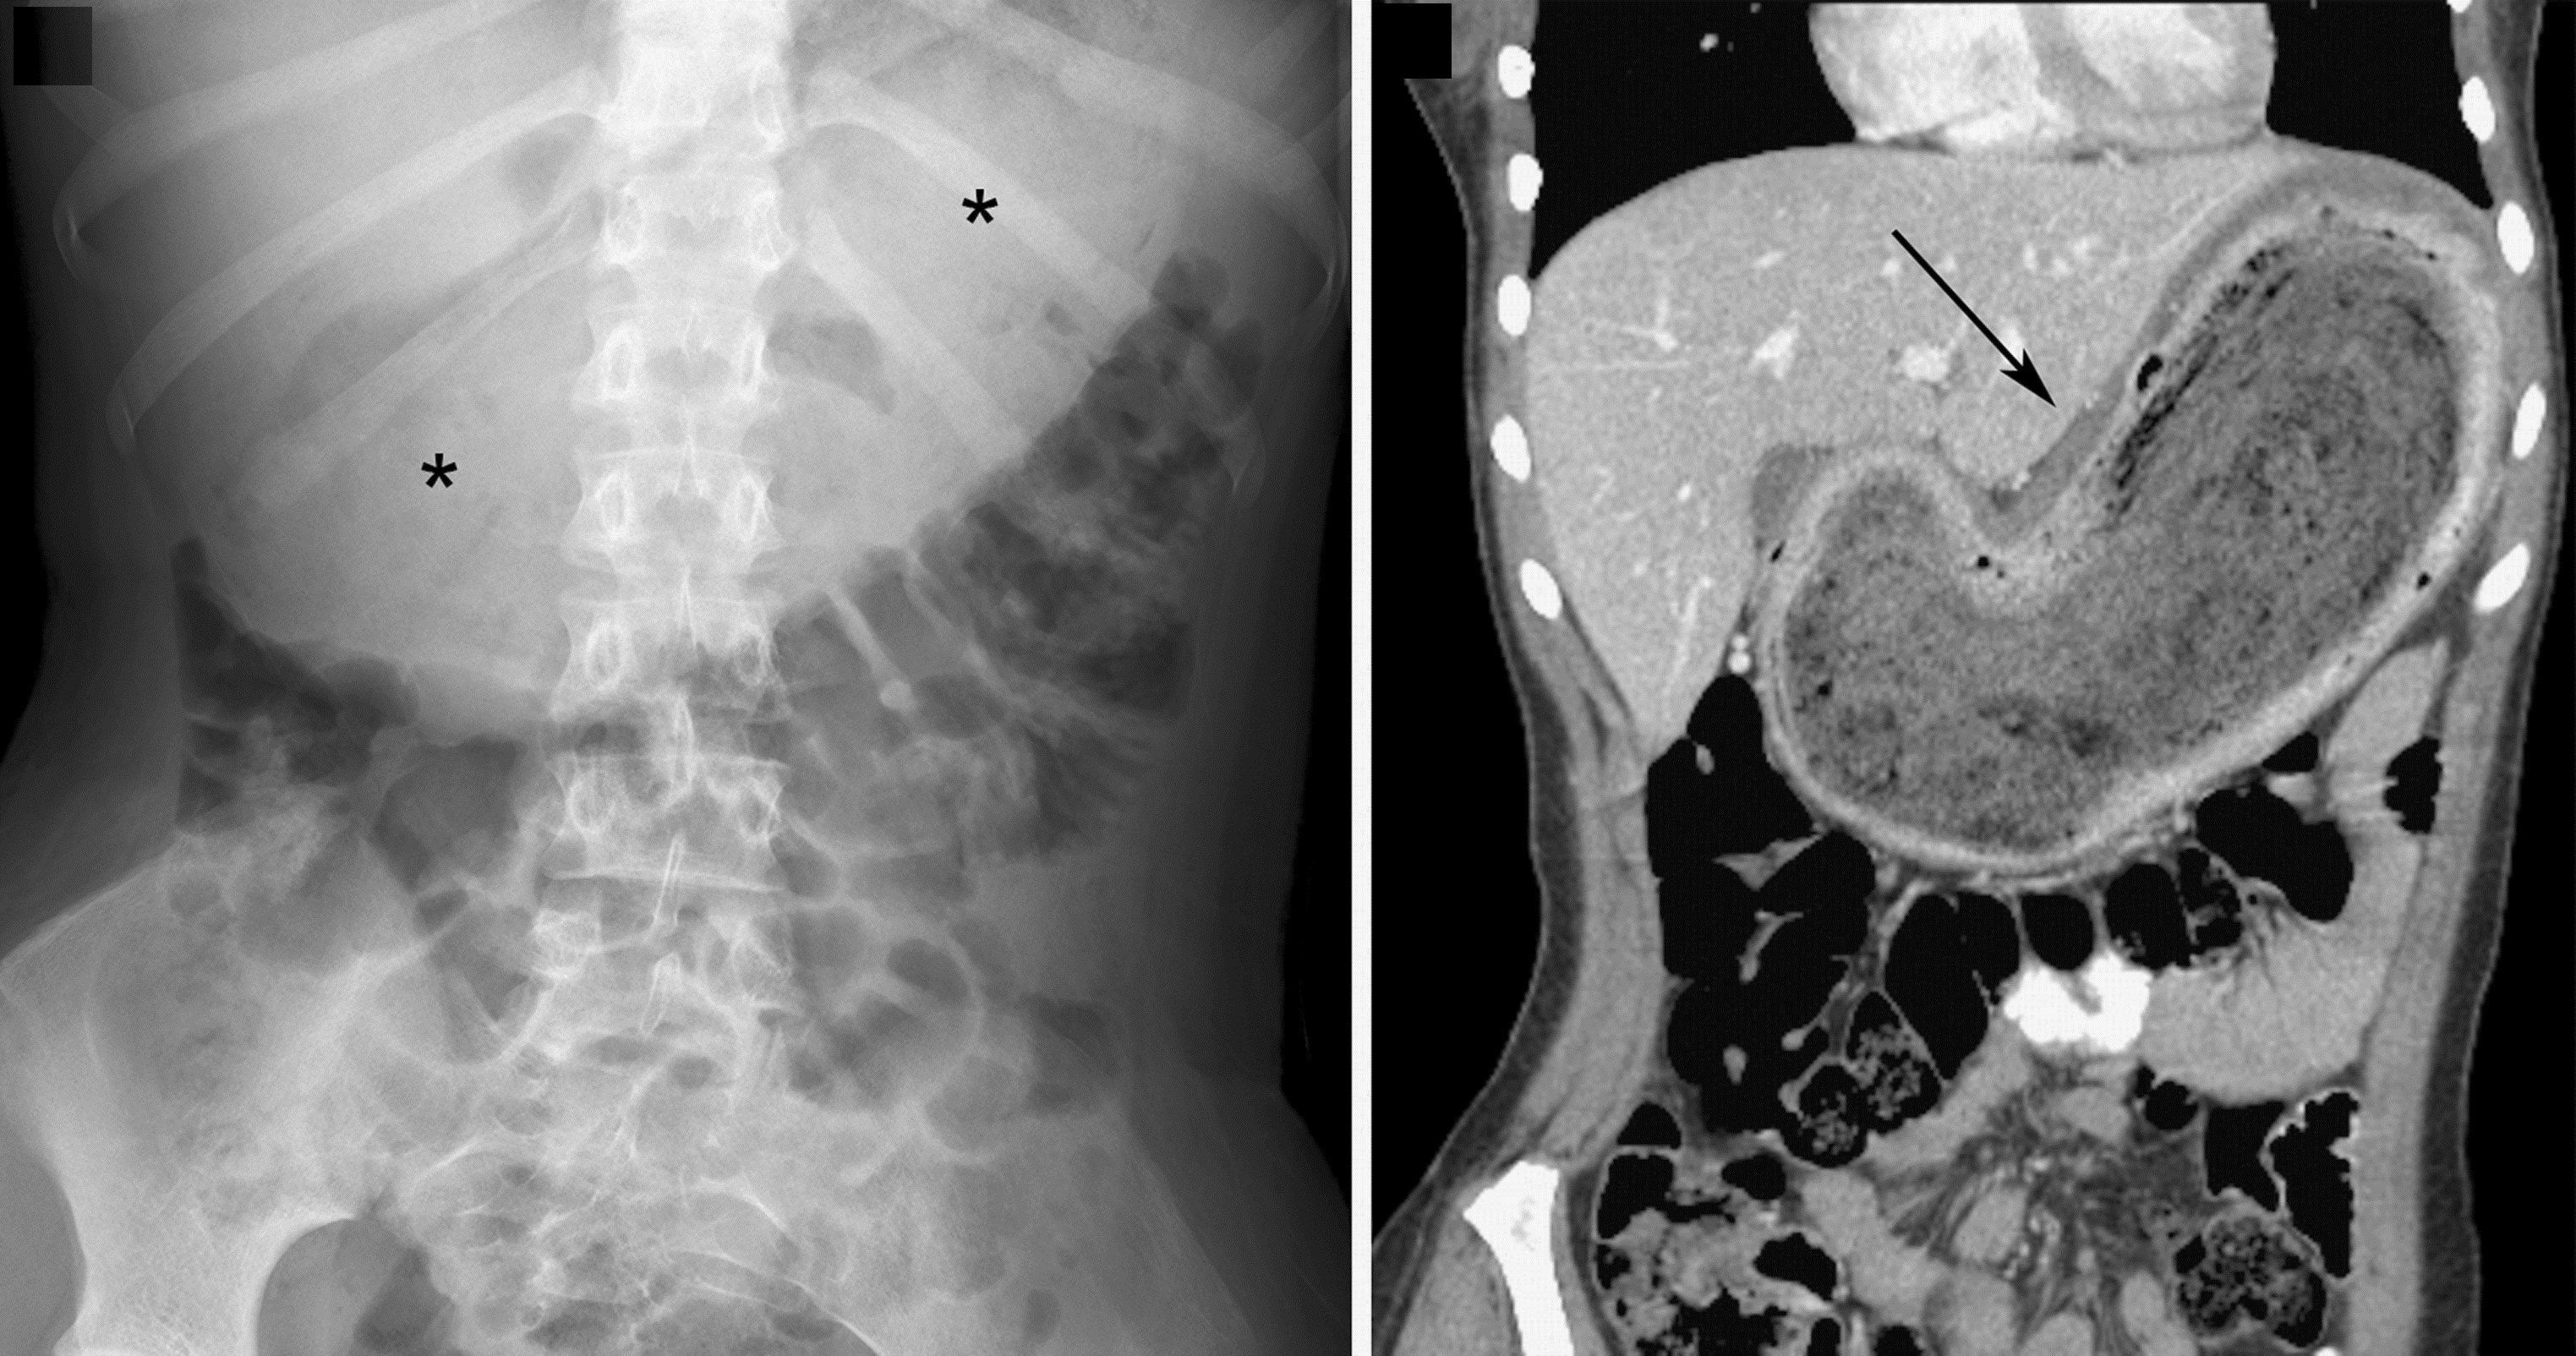

phytobezoar develops when large quantities are ingested and accumulate. Trichobezoars occur most commonly in young women and children from ingestion of large amounts of hair, carpet fiber, or clothing fiber. Trichobezoars are more often associated with psychiatric disorders, mental retardation, or pica.